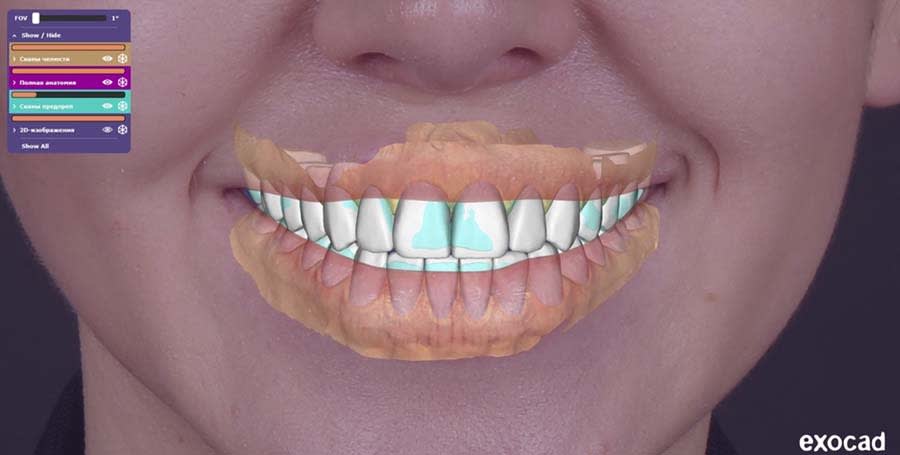

Laboratory Stage

The final restoration design was created in CAD software. Based on scans of the provisionals and the approved wax-up, the final design was completed factoring in soft-tissue contours post-gingivectomy and adjustments in tooth length and proportions. Other considerations in the restoration design included the maintaining of functional occlusion from the provisional restorations and the integration of CAD articulator parameters.